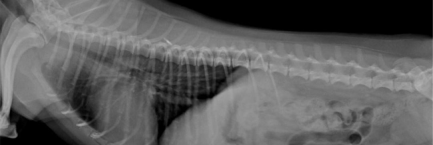

흉복부 방사선검사와 필요할 경우 초음파검사

마취를 하는데 문제가 될 수 있는 심장질환, 호흡기 질환, 소화기 질환, 종양 유무를 확인하기 위해서 흉부와 복부 방사선 촬영 검사가 필요합니다.